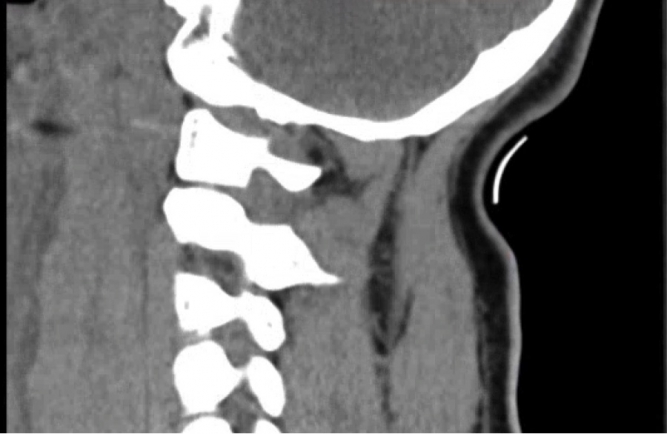

A 29 yo male presents from a high speed MCV. He was the unhelmeted driver of a motorcycle. He was unresponsive and intubated prior to arrival. CT of the cervical spine is shown below. What's the diagnosis? Scroll down for answer

Answer: Atlanto-occiptal dislocation (internal decapitation)

- Mechanism is hyperextension/distraction

- Lateral cervical spine xrays may be unremarkable aside froom pre-vertebal swelling

- CT plus MRI are used to evaluate ligamentous injury